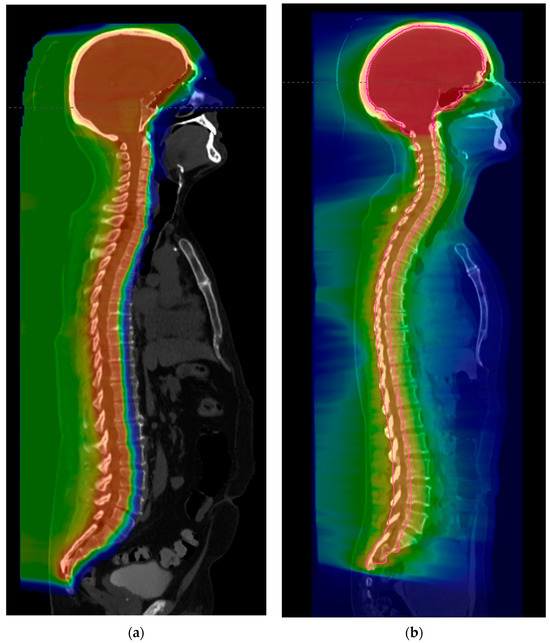

- Prabhu, R.S.; Dhakal, R.; Piantino, M.; Bahar, N.; Meaders, K.S.; Fasola, C.E.; Ward, M.C.; Heinzerling, J.H.; Sumrall, A.L.; Burri, S.H. Volumetric Modulated Arc Therapy (VMAT) Craniospinal Irradiation (CSI) for Children and Adults: A Practical Guide for Implementation. Pr. Radiat. Oncol. 2022, 12, e101–e109. [Google Scholar] [CrossRef] [PubMed]

- Sener, U.; Webb, M.; Breen, W.G.; Neth, B.J.; Laack, N.N.; Routman, D.; Brown, P.D.; Mahajan, A.; Frechette, K.; Dudek, A.Z.; et al. Proton Craniospinal Irradiation with Immunotherapy in Two Patients with Leptomeningeal Disease from Melanoma. J. Immunother. Precis. Oncol. 2024, 7, 1–6. [Google Scholar] [CrossRef] [PubMed] [PubMed Central]